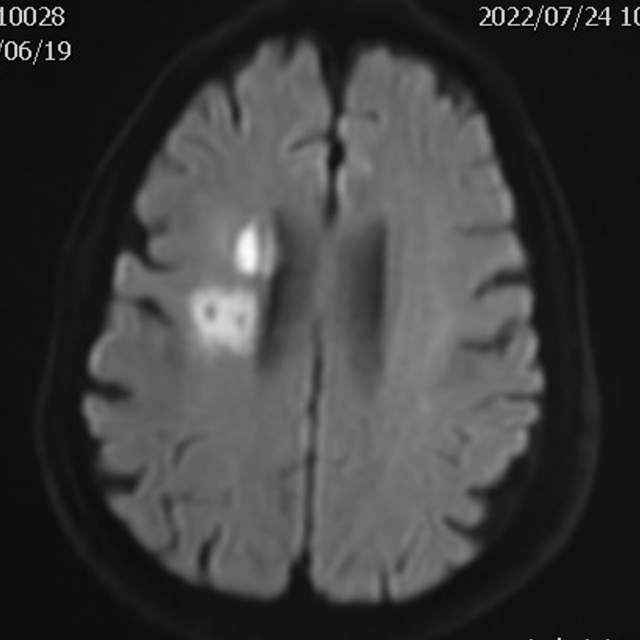

78岁老年男性,最近一个半月来已经和家里人没法正常交流,认知能力大幅下降,在农村,可能也就认为年龄大了,听天由命了。可老人家就是福大命大,有亲戚做医生,间隔17天先后为老人做了两次头颅MRI,发现脑梗塞,右侧血管长节段严重狭窄,右侧大脑半球缺血严重(图6,满江红),手术风险大……,家属经过反复咨询、犹豫、权衡,选择了保守治疗,毕竟老人年龄大了,手腿现在还能动,手术也有风险,时机也不是太好,国外研究不推荐,国内研究也不支持,保守治疗似乎是个不错的选择。然而,保守期间,患者反复出现脑梗塞,认知能力进行性下降,最终促使家属决定采用外科干预。然而,对医生而言,在梗塞的急性期处理这种长节段密布分支血管的病变风险不言而喻,而一味的观望和等候肯定不是最佳选择。过一点,可能出血;欠一点,可能闭塞。全面认真评估后,我们顺利为老人家完成了I期治疗,老人家的“火焰山”(图6)变成了“绿油油”充满生机的田野(图14),缺血明显改善,认知能力大幅提高,术后就能和家人正常交流了,也记起了很多以前忘记的事情……,家人很开心。